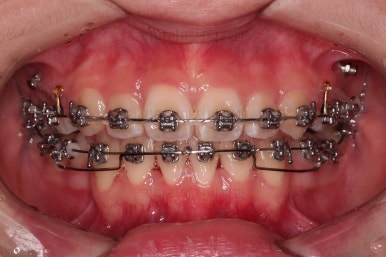

장치 부착 직후의 모습인데요.

웃을 때의 느낌, 장치 때문에 입이 튀어나오는 정도 등 참고해주세요.

적절한 시기에 발치를 하고요.

치열이 우선 가지런해졌다면 미니스크류를 이용해서 앞니를 뒤로 당겨주게 됩니다.